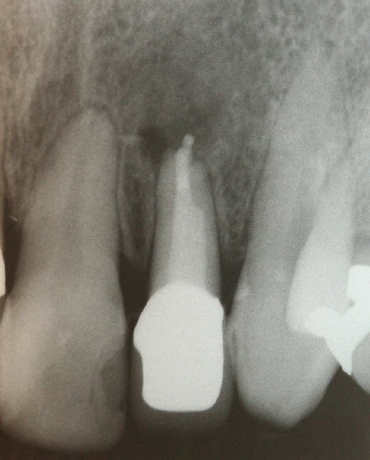

初診時

コアをはずして根管治療